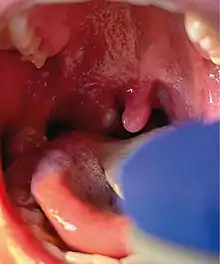

Mpox is a viral infection that manifests a week or two after exposure with fever and other non-specific symptoms, and then produces a rash with lesions that usually last for 2–4 weeks before drying up, crusting and falling off.[10] While mpox can cause large numbers of lesions, in the current outbreak, some patients experience only a single lesion in the mouth or on the genitals, making it more difficult to differentiate from other infections.[22] In infections before the current outbreak, 1–3 per cent of people with known infections have died (without treatment). Cases in children and immunocompromised people are more likely to be severe.[23]